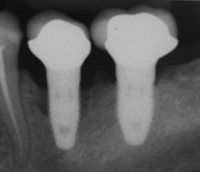

Peri-implantitis

Bone loss (peri-implantitis) on implants over 7 years in a heavy smoker